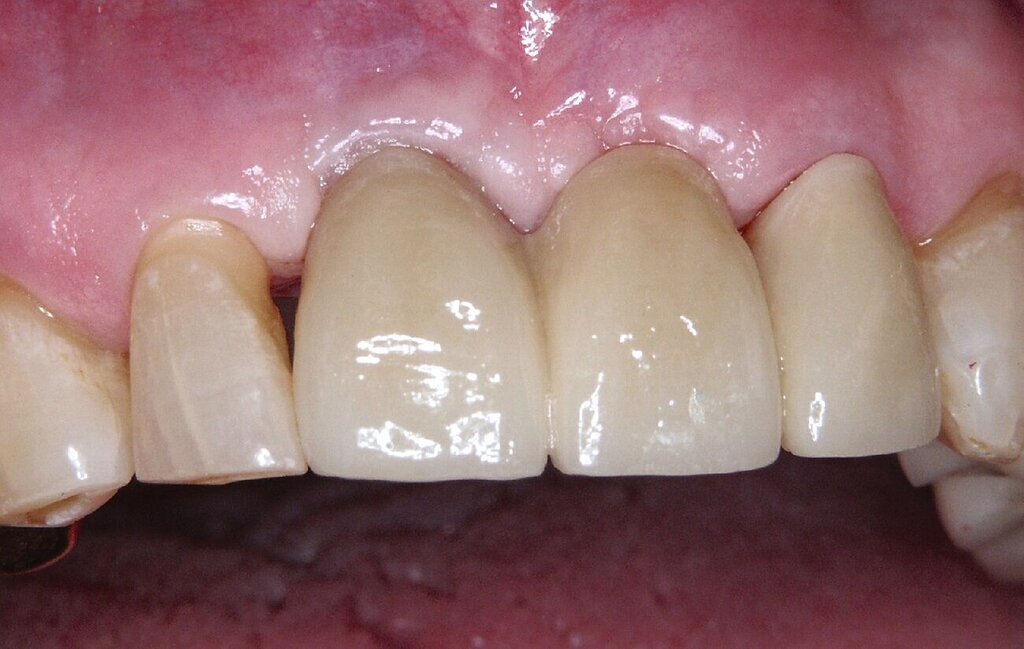

Bei einem 76-jährigen Patienten wurde ein circa 20 Jahre altes Aluminiumoxid-Implantat (Abb. 2a) entfernt, nachdem die ausgeprägte Gingivarezession in Kombination mit dem Abbau der vestibulären Knochenlamelle keine ausreichende Mundhygiene mehr zuließ. Nach Entfernung der Krone auf dem intakten Implantat in regio 11 konnte zur provisorischen Lückenversorgung eine stuhlgefertigte, kombiniert Zahn/Implantat-gestützte Brücke von 011 auf 22 eingegliedert werden (Abb. 2b). Eine Nachimplantation war aufgrund der günstigen Prognose für den Pfeilerzahn 22 überflüssig. Das verbliebene Weichgewebsdefizit wurde drei Monate nach der Explantation mit einem Bindegewebstransplantat vom harten Gaumen kompensiert (Abb. 2c bis 2e). Nach einer Konsolidierungsphase von weiteren drei Monaten wurde das Provisorium durch eine monolithische Zirkoniumdioxidbrücke mit ausschließlich vestibulärer Verblendung ersetzt (Abb. 2g). Eine invasive knöcherne Augmentation mit Wiederherstellung des knöchernen Kieferkamms nach dem Implantatverlust in regio 21 konnte vermieden werden, da eine erneute Implantation für das Behandlungsziel einer festsitzenden Versorgung nicht nötig war.